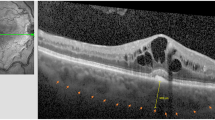

The Sturge–Weber Syndrome (SWS) is a phacomatosis which include facial nevus flammeus, glaucoma, diffuse choroidal hemangioma, and leptomeningeal hemangiomatosis. External beam radiotherapy (EBRT) using photons was used to treat retinal detachment. We investigate the anatomical and functional results in a long-term basis.

Retrospective review of SWS patients treated by EBRT (20 Gy in 10 fractions) for an exudative diffuse choroidal hemangioma. Visual acuity, B-scan tumor thickness, size of retinal detachment, intra-ocular pressure, and hypotonic treatment were collected before EBRT, 1 year after, and at the latest news.

Twenty-five patients (26 eyes) were treated between 2001 and 2014. Retinal detachment including the macula was found among twenty-six eyes before treatment. The average follow-up time was 47 months. The mean tumor thickness was initially 4.5 mm, 2.8 mm at first year, and 2.7 mm at the last visit. The retina was reattached at the last visit for all eyes except two. The visual acuity was stable or better for 20 eyes (p = 0.02). Four patients developed mild cataract during the follow-up.

EBRT using 20 Gy in 10 fractions is efficient, decreases tumor thickness, reattaches the retina, and stabilizes visual acuity. In the long term, retinal reattachment allows ocular conservation by preventing phthisis bulbi.